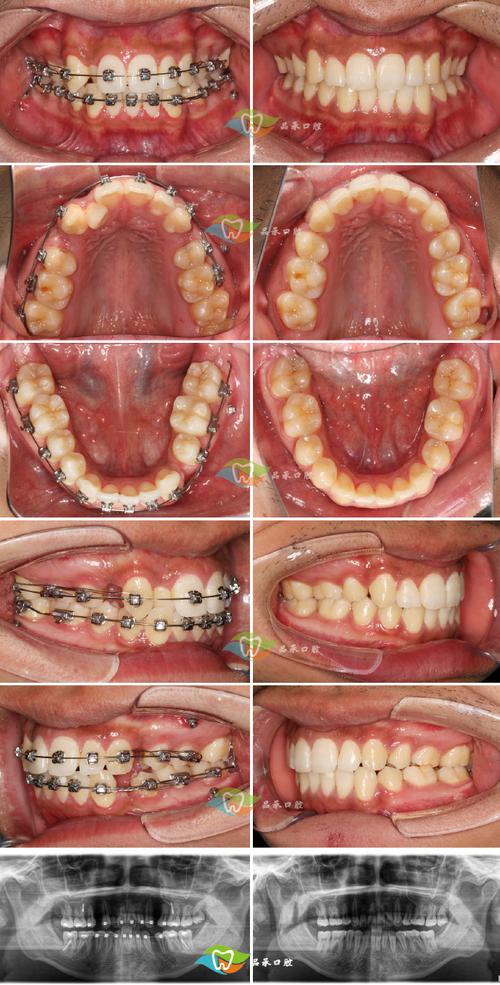

| 固定矫治器+螺旋弹簧 | 在固定托槽(如金属托槽、陶瓷托槽)间植入螺旋弹簧,通过弹簧弹力推开牙齿。 | 单颗或多颗牙间隙不足,需精准控制牙齿移动方向。 | 优点:力量可控,适用范围广;缺点:口腔卫生维护难度增加,需定期复诊调整。 |

当间隙达到设计要求后,医生会进入“间隙关闭阶段”,通过弓丝、橡皮筋等将牙齿移动至目标位置,最终实现牙齿整齐、咬合稳定,间隙关闭后需佩戴保持器(如透明保持器、固定保持器),因为牙齿移动后,牙周纤维和牙槽骨需要时间重建稳定性,若不戴保持器,间隙可能复发(尤其是成人患者)。